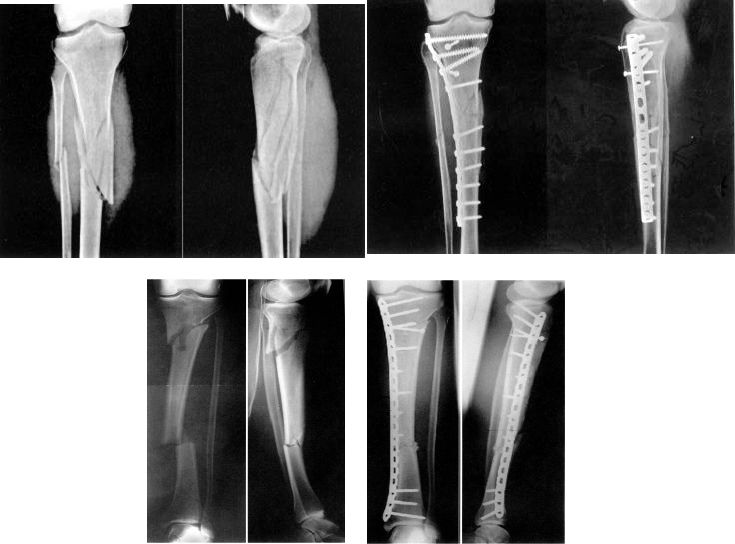

La réduction précoce et la fixation interne sont privilégiées pour les fractures ouvertes et fermées, en particulier pour celles compliquées de lésions vasculaires, nerveuses ou tendineuses, la chirurgie doit être effectuée immédiatement.

Déterminer la nature de la violence liée aux blessures

Les blessures à haute énergie sont souvent accompagnées de lésions graves des tissus mous.Elle se caractérise par un gonflement des membres, des cloques, une abrasion cutanée et une lacération cutanée.L'opération doit être reportée pour le moment.Dans le même temps, le syndrome de l'espace fascial et les lésions vasculaires et nerveuses doivent être exclus.

La particularité de l'anatomie - l'importance de la couverture des tissus mous.

Stade précoce : dans les 8h

Le fixateur externe est considéré comme le premier choix pour un traitement précoce.

Support de gypse

Traction calcanéenne

Phase II : environ 2 semaines.

Il n'y avait pas d'infection systémique évidente ni de traumatisme aigu.

Pas de gonflement ni d'exsudation de la plaie.

L'ampoule est sèche, le gonflement diminue et les marqueurs osseux peuvent être touchés.

Peau ridée, des lignes de peau apparaissent.

Le résultat du traitement de la fracture de Pilon dépend de la qualité de la reconstruction articulaire et de l'état de la couverture des tissus mous.

Le meilleur moment pour la chirurgie dépend de l'état des tissus mous :

Stade précoce : l'opération a été réalisée en 6 ~ 8h, qui a duré 2 ~ 3h.

Délai : 7 ~ 10 jours, le gonflement a disparu et les rides de la peau sont apparues.